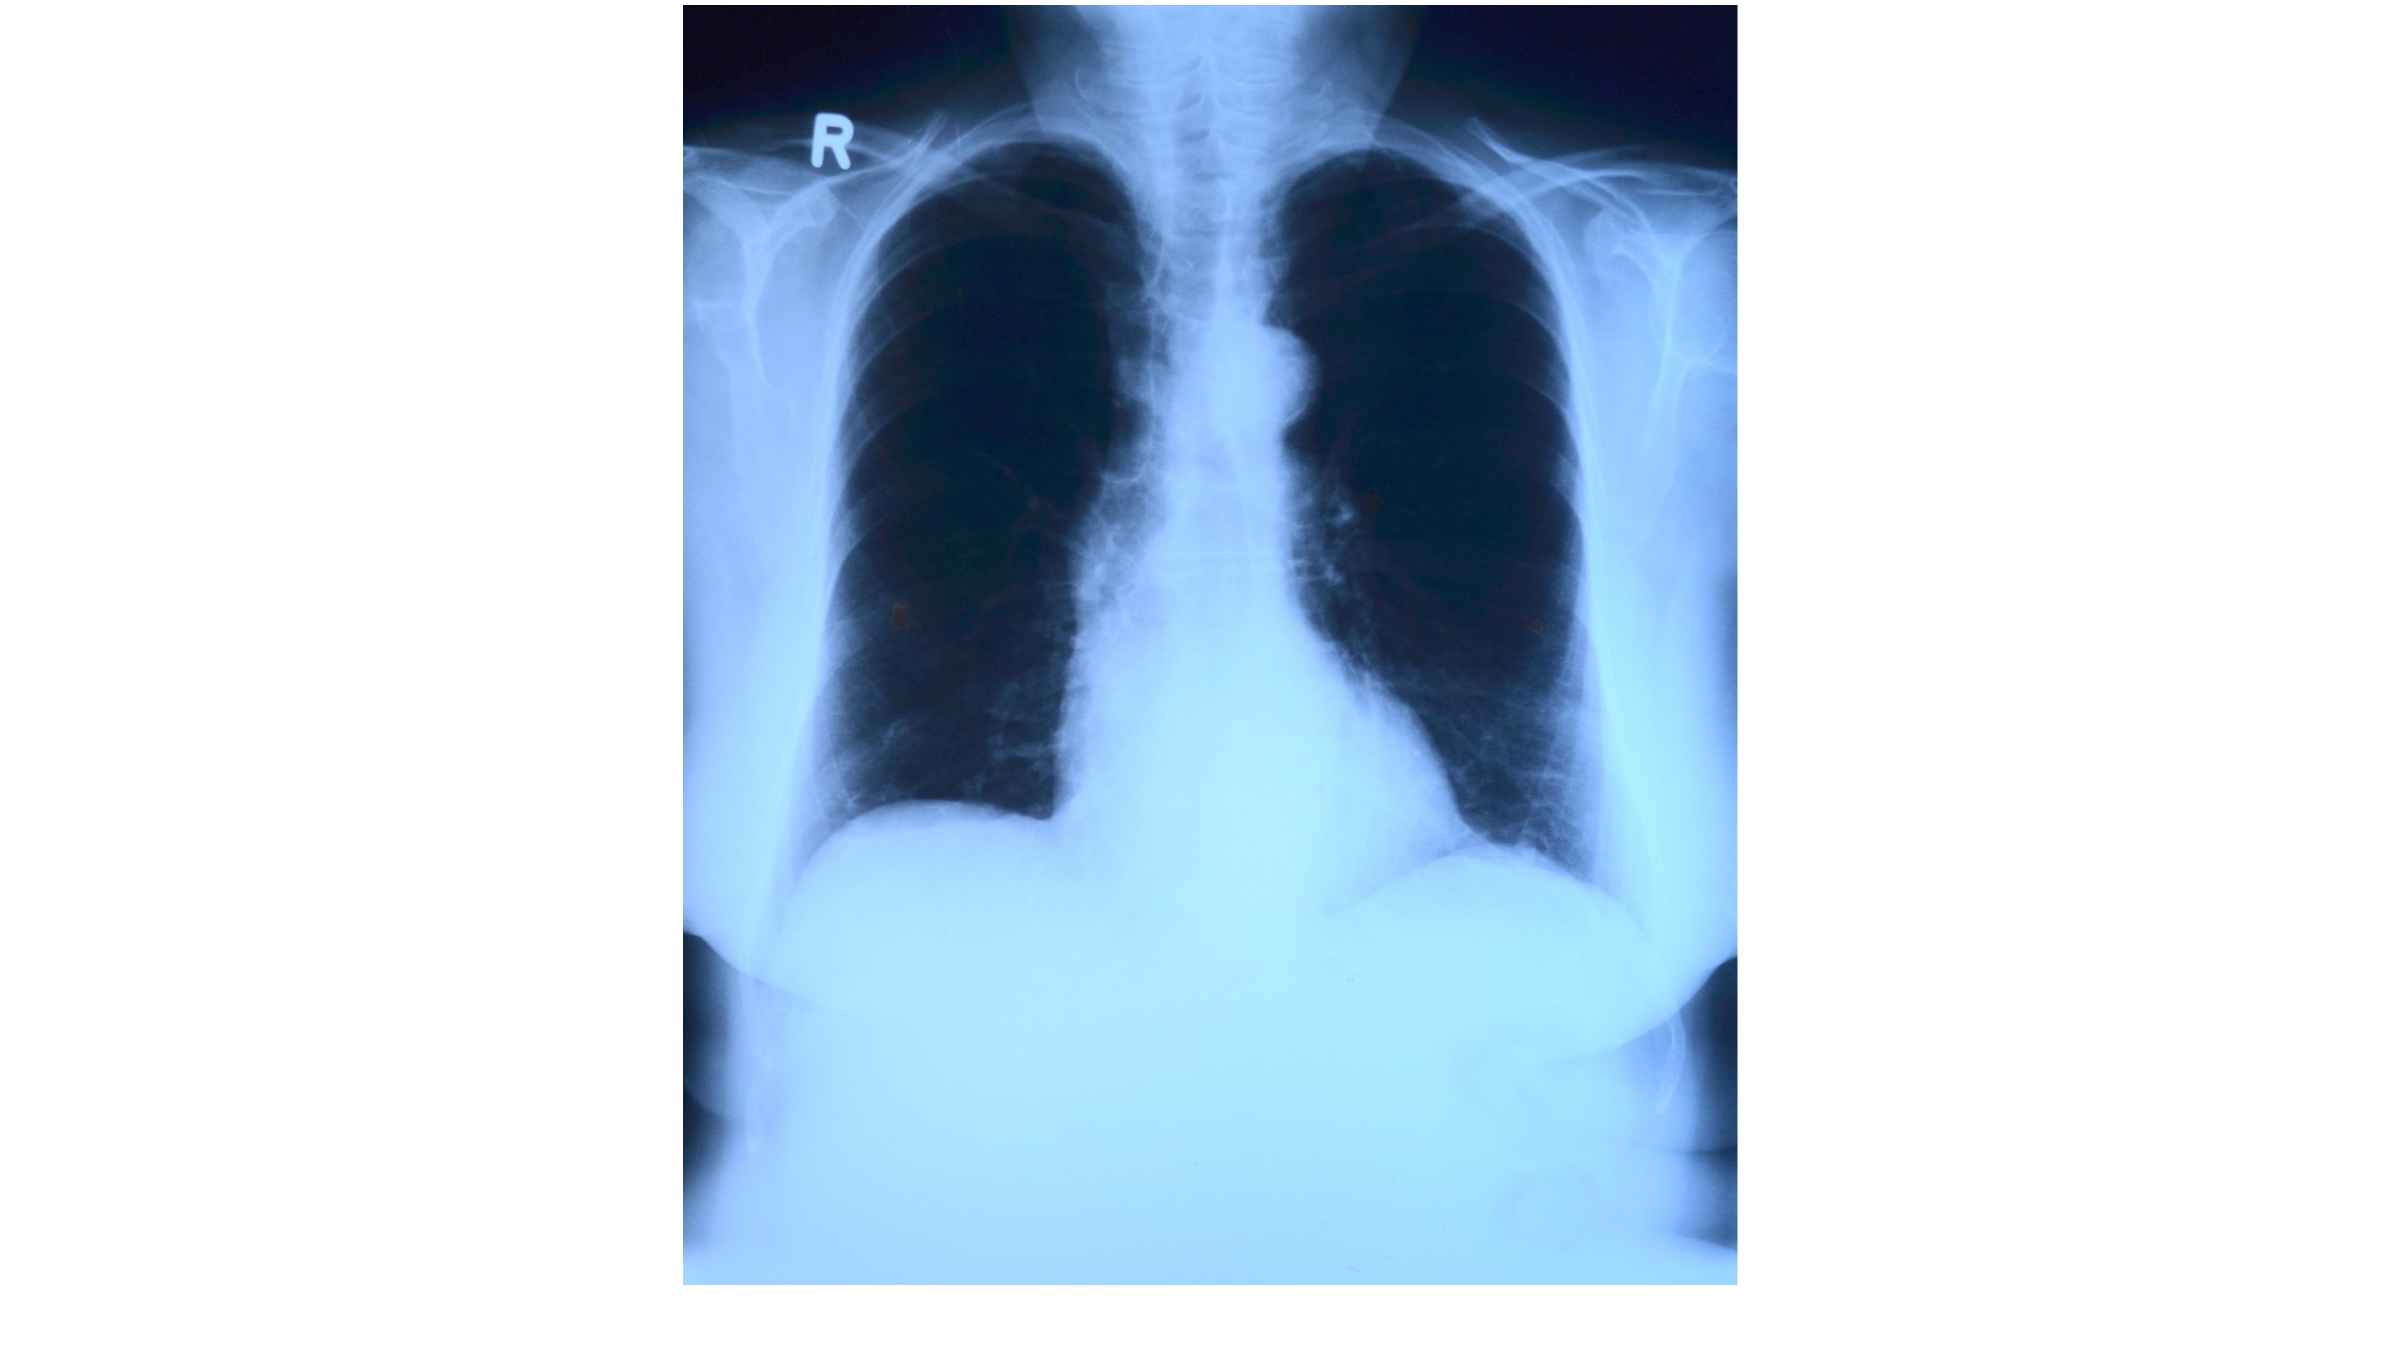

Le pneumothorax spontané primaire est défini comme de grande abondance lorsqu’il existe un décollement sur toute la ligne axillaire, d’une largeur de plus de 2 cm au niveau du hile sur une radiographie de thorax de face en inspiration.

Figure 1 : Algorithme de prise en charge du pneumothorax spontané primaire sans signe de gravité, inspiré des nouvelles recommandations